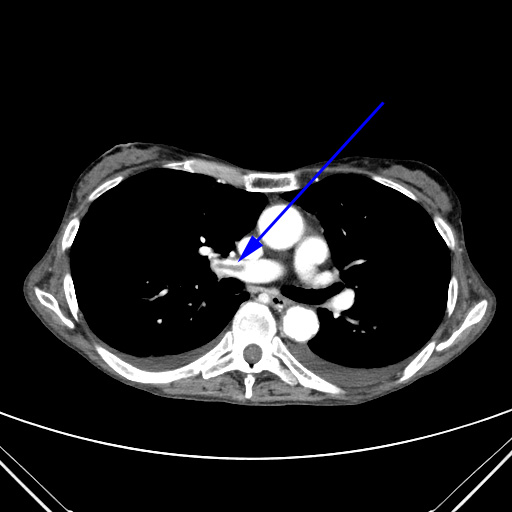

CT-skanning af thorax med intravenøs kontrast viser en blodprop (blå pil) i arterien til den højre lunge.